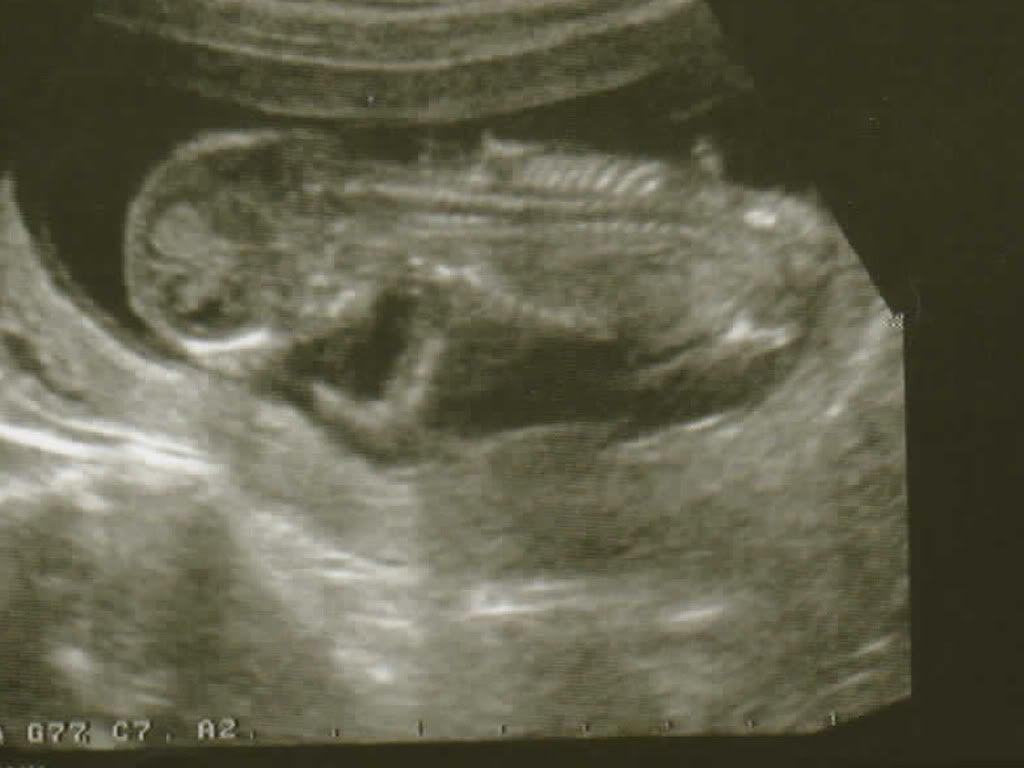

Le gynécologue me prend donc, je lui parle un peu de mes angoisses et nous faisons l’écho des 3 mois. P’titPou nous montre sa belle colonne vertébrale

Nous avons vu son petit coeur et son estomac, ses jambes se sont un peu dépliées dans un sursaut. Et puis aussi ses mains. Il s’est gratté son menton et mis un doigt dans le nez. Son crâne fait 2,5 cm. C’est petit hein !! Sa taille fait environ 8 cm de la tete au coccix.

Cela m’a soulagé. Le gynécologue m’a aussi rappelé que le fait de ne pas le sentir était normal à ce stade et aussi qu’il était encore bas. Le placenta est correct.